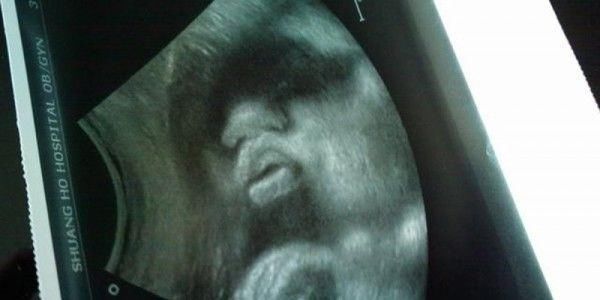

小希第一胎生的女儿,所以这次怀孕一家人都希望能生个儿子呢。小希想到自己的闺蜜就是在妇产科的,就直接找她就好了,在小希怀孕5个月时候,闺蜜告诉小希肯定是个女孩,没有看到宝宝两腿之间有凸起的东西。这让小希有点失望了,回去和家人说是个女娃后,一家人都说两人女儿也好,没什么压力,都同意把孩子生下来,小希想着都5个月了,去引产的话她不忍心。

到了第六个月了,小希没有找自己的闺蜜了,而是去了另一家医院产检,在检查的时候,小希就随便说了一句,我闺女在里面干嘛呀?医生诧异了,笑着说:孩子一切正常,多了一跳腿!

顿时把小希吓蒙了,第一次产检是明明说是个女儿的,这次又说孩子正常,多了条腿。把医生的话告诉家人后,全家人都蒙了,不知道医生的话是什么医生,每个人的心里都很忐忑。终于到了小希临产的时候,孩子生下来后,全家人都乐了,居然是个儿子,小希和家人这才明白医生的话了,小希内心非常的高兴和激动。